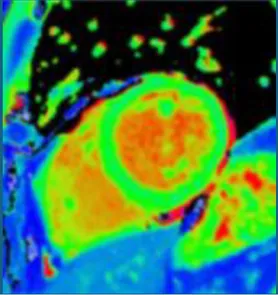

Synthetic post-contrast imaging

Contrast-free “synthetic LGE” has been developed through the use of generative adversarial networks (GANs). Two leading techniques have been developed: “virtual native enhancement (VNE)” (1, 2), which has native T1 maps and cine MRI as inputs, and has been applied to chronic myocardial infarction (MI) (2) and HCM (1), and “cine-generated enhancement (CGE)”, which identifies LGE from cine MRI only and has been applied to acute MI (16). Both techniques demonstrated potential to detect the respective pathologies tested. Furthermore, infarct VNE has been validated ex-vivo in porcine models (2).

Moreover, as for LGE, GANs have also been used to generate virtual contrast-enhanced T1 maps using native (contrast-free) T1 map inputs for virtual ECV mapping (vECV). vECV showed good agreement with conventional ECV in healthy volunteers and myocarditis but was more modest in cardiac amyloidosis. Authors also noted some focal mapping abnormalities were not recapitulated using vECV and some lesions were “hallucinated” a known hazard of GAN based deep learning. Nevertheless, the study determined proof-of-principle for virtual ECV to expand this valuable diagnostic tool to patients otherwise precluded from GBCA and faster and cheaper CMR (27).